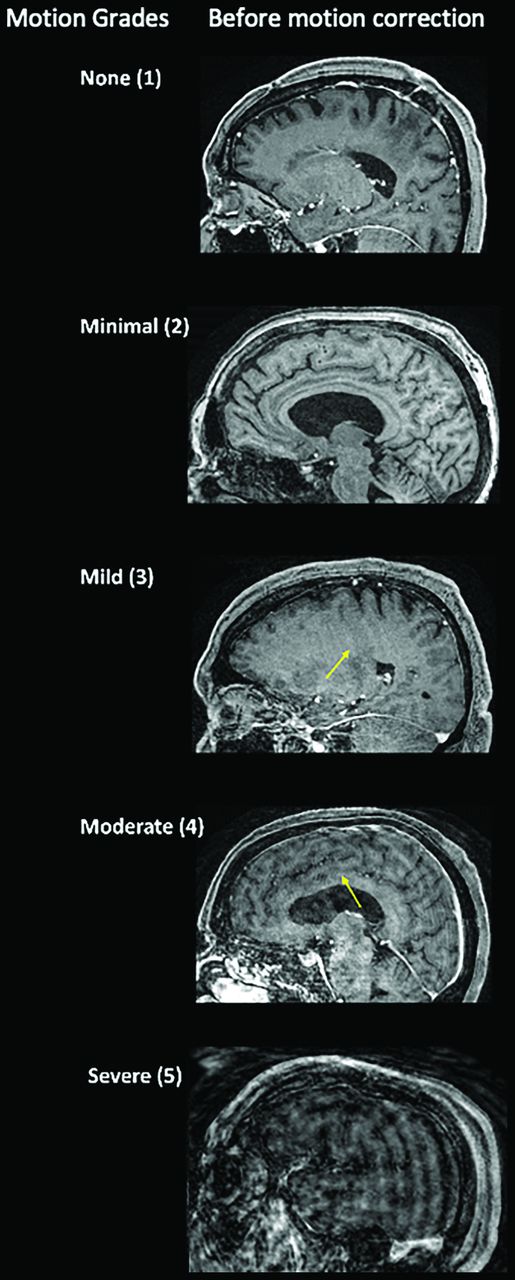

In baseline nondiagnostic cases of moderate or severe motion (motion grades 4 or 5, respectively), SAMER motion correction reduced motion artifacts in 87.5% (14/16) of cases (Fig 3), which included 100% of moderate motion cases (grade 4) and 75% of severe motion cases (grade 5). In fact, 11 of the 16 nondiagnostic grade cases (69%) were considered diagnostic in quality after SAMER motion correction, ie, they were reduced from a score of 4 or 5 to a score of ≤3. Representative images comparing cases with severe motion before and after SAMER motion correction are provided in Fig 4. For cases with minimal, mild, moderate, and severe motion, SAMER improved the motion grade by an average 0.13 (SD, 0.7), 0.3 (SD, 0.5), 1.1 (SD, 0.25), and 1.1 (SD, 0.83) grades, respectively (Table 2).

Axial MR images of 2 cases with severe motion artifacts (grade 5) in which SAMER motion correction restored diagnostic value (by reducing motion grade to 3). A, The extent of cortical/gyral enhancement (arrows) and edematous expansion of the left temporoparietal region with a mild rightward mass effect is better visualized on the motion-corrected image of a 67-year-old man with traumatic brain injury. B, Motion-corrected image shows better visualization of cortical laminar necrosis in the left occipital lobe (arrows) and better evaluation of left temporal lobe volume loss (arrows) in an 86-year-old woman with history of stroke.